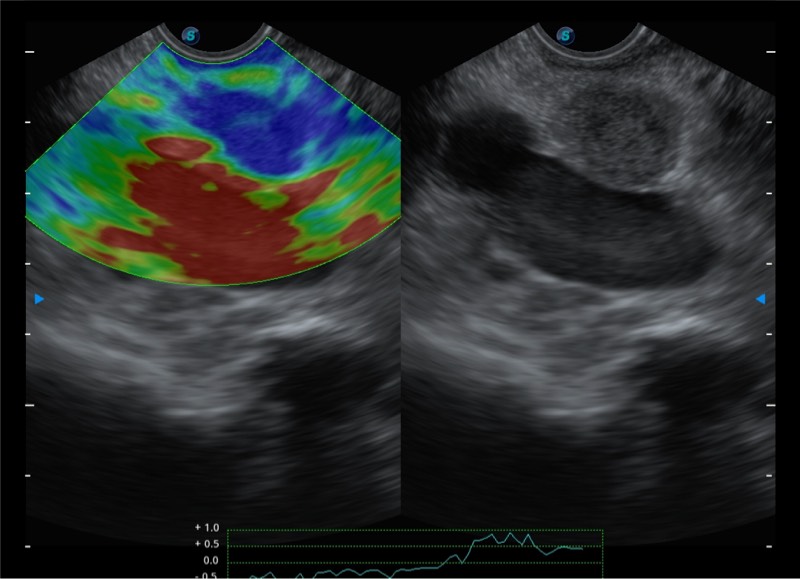

高端超声影像平台

基于二十年的超声技术积累,开立提供了最新一代的独立超声主机,在提供高质量图像的同时满足多学科使用。具备常见多普勒技术并提供弹性成像、声学造影等高端影像技术。新一代传感器具有更强的抗干扰能力并减少图像伪影。